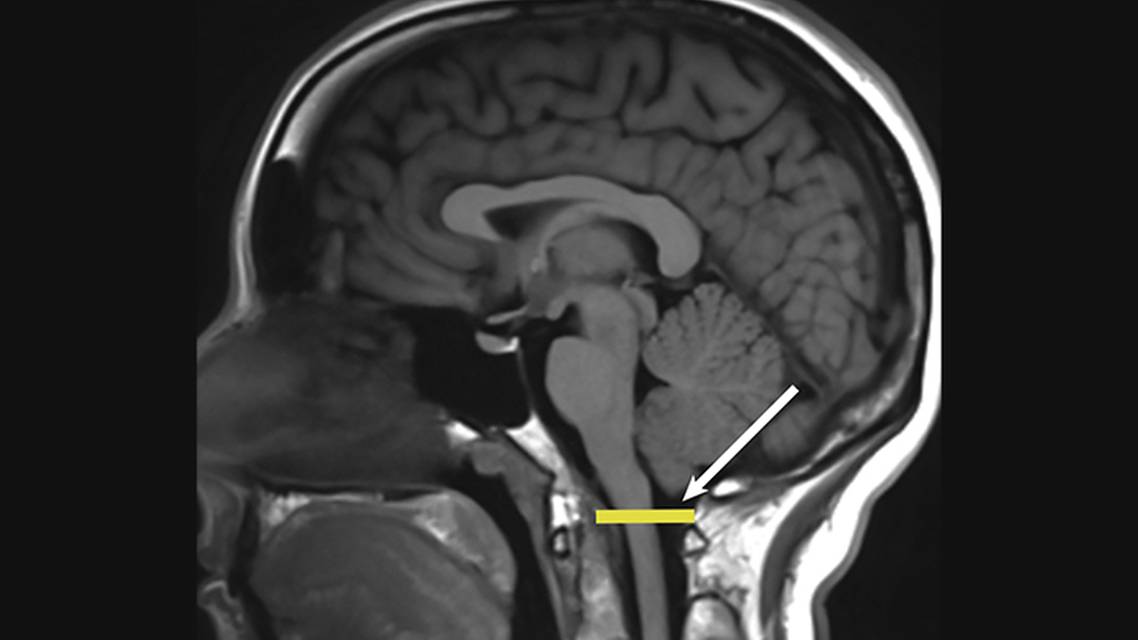

Chiari malformations comprise a spectrum of congenital hindbrain abnormalities that affect the structural relationships among the cerebellum, lower brain stem, upper cervical spinal cord, and the foramen magnum within base of the skull (craniocervical junction). The foramen magnum is an oval-shaped opening in the skull base. Normally, only the medulla extends below the foramen magnum, where it merges seamlessly with the cervical spinal cord. In Chiari malformations, the cerebellar tonsils descend more than 5 mm below the level of the foramen magnum (Figure).

Chiari type I malformations (CM-I) are characterized by abnormally shaped cerebellar tonsils displaced more than 5 mm below the level of the foramen magnum. Normally, only the spinal cord descends through the foramen magnum (Figure). CM-I is the most commonly encountered Chiari malformation. The prevalence of CM-I in the US is approximately 0.1% to 0.5%, with the number of new cases diagnosed each year ranging from 5.5 to 78 cases per 100,000 people.3,4 CM-I has a slight female predominance of 1.3:1.